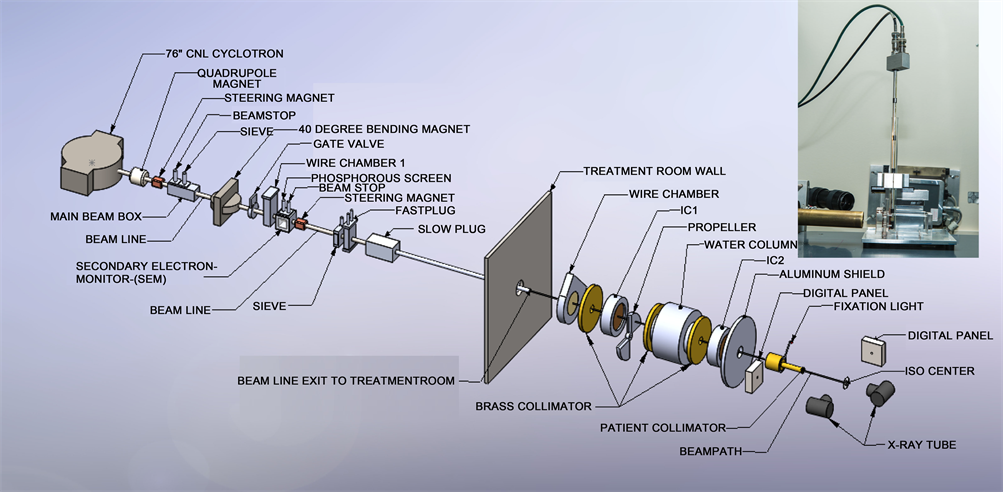

All measurements were made on the eye therapy beam line at Crocker Nuclear Laboratory, UC Davis. The beam line is outlined earlier [16] and is briefly described here. The 76-in isochronous cyclotron at UC Davis accelerates protons to a maximum energy of 67.5 MeV. The beam travels through several devices before entering the treatment room and irradiating the patient at the iso-center. The beam after extracting from the cyclotron passes through quaderpole, steering magnet. The beam is directed to 40-inch magnet, which sends the beam in different beam lines. After 40-in magnet, the beam passes through wire chamber and secondary emission chamber (SEM). After exiting the cyclotron, the beam is focused by two quadrupole magnets. The beam is then steered by X-Y dipole magnets to the center of the 10-cm aluminum beam pipe. A 40-inch dipole magnet deflects the beam to any of the 6 beam lines at the CNL cyclotron. The beam line at 9˚ transports the beam to the eye therapy cave. The eye beam line set up is illustrated in Figure 1. The vacuum beam pipe ends at the entrance to the treatment room. The beam extraction from the cyclotron is optimized at beam stop 2b and the beam position in the horizontal and vertical planes is

Figure 1. Layout of ocular beam line at UCSF-CNL Eye Treatment Facility. The beam, after entering the treatment room, passes through several devices before radiating the patient at the iso-center. The insert in the figure shows the experimental setup at the iso-center.

measured with wire chamber 1 (WC1), which is placed downstream of the 40-inch bending magnet. The beam size and beam position are monitored in the treatment room by wire chamber 2 (WC2). WC1 and WC2 each have 2 orthogonal planes with 2 mm and 6 mm wire spacing, respectively.

The chair is placed at the iso-center for final positioning. A head holder to position the patient’s head is attached to the chair. The base of the chair can be rotated through 360˚. The chair moves in three orthogonal directions. There are two x-ray tubes, one placed in the posterior direction, just behind the chair, and one in the lateral direction. There are two flat panel digital imagers [22] . The digital panel in the anterior-posterior direction is placed on the beam line at a fixed target-to-image distance of 1190 mm. It is attached to the patient assembly system. This imager is mounted on an air piston and interlocked to the X-ray unit. When making an exposure, the imager is in-line with the center of the focal spot and with the iso-center. The imager moves up and stops at the required position when the X-ray enable trigger is depressed. The imager returns to the parked position, which is outside of the radiation field when the X-ray button is released. The imager in the lateral direction is placed at a fixed target-to-image distance of 2000 mm, as shown in Figure 1.